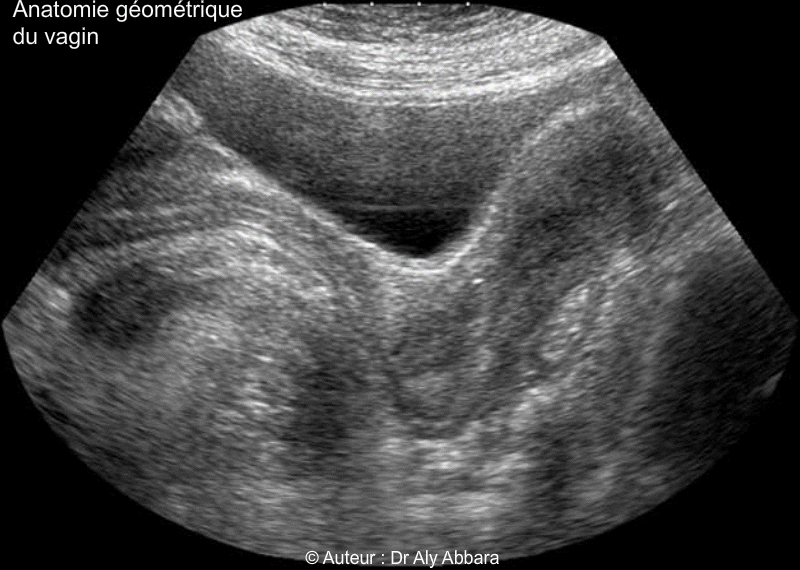

Vagin de femme adulte - Rapports anatomiques - Echographie

(Coupe échographique sagittale médiane du pelvis - vessie semi-pleine).

• Morphologiquement le vagin est plus étroit au niveau de son tiers inférieur, près de la vulve, puis il s'élargit au niveau de son tiers moyen et surtout au tiers supérieur, cette étroitesse relative dans la portion vaginale située près de son entrée vulvaire est due à la présence des fuseaux musculaires des muscles releveurs de l'anus qui encerclent cette partie du vagin en arrière et bilatéralement. Cet encerclement musculaire donne au vagin une forme coudée, donc en position allongée, sur un plan sagittal médian, la partie basse du vagin est oblique (de l'arrière en bas vers l'avant en haut), la partie haute du vagin se dirige vers l'arrière. L'angle formé par les deux axes du vagin est un angle obtus, ouvert vers le bas (en position allongée) et sa valeur est égale à environ à 140 degrés.